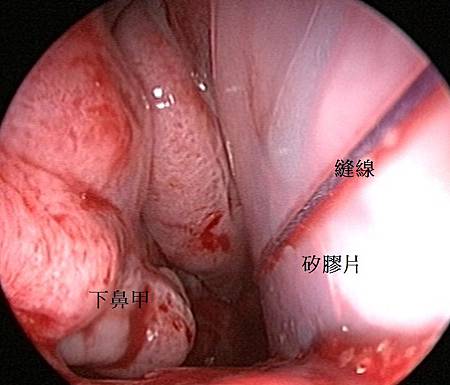

5. 保護與固定: 縫合後需在鼻中隔兩側縫上兩片矽膠片(Silicon sheet),約 7–10 天後拆除。